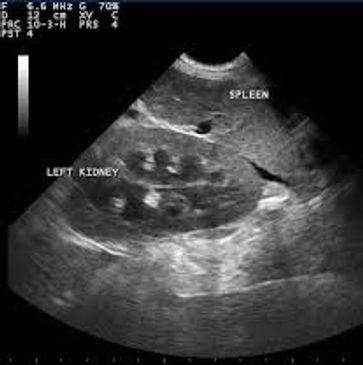

In house ultrasonography help in diagnositics of abdominal problems such as tumours, kidney conditions, bladder stones and glandular changes.

We also offer pregnancy ultrasound imaging to confirm pregnancy and help approximate the due date.